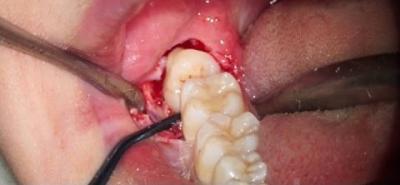

- Надрез десны, отслоение её от кости, осуществляется, чтобы добраться до удаляемого зуба и его корней.

-

Распиливание зубной единицы на несколько частей с последующим извлечением из мягкой ткани, выполняется с целью облегчения экстракции массивной восьмёрки.

В случае когда корни сломаны в процессе извлечения, их удаляют по отдельности.

- Очищение лунки от скоплений крови, её тщательный осмотр на предмет присутствия осколков зуба или корневой системы.

- Установка дренажа для очищения раны от гноя (при его наличии) с последующей обработкой лунки антисептиком.

- Зашивание рассечённой десны посредством наложения саморассасывающихся швов.